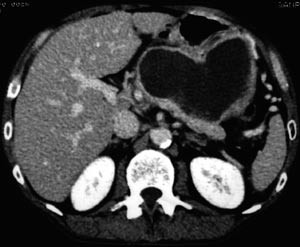

I tillegg til teksten er studiane vurdert systematisk i e-tabell 2 (5, 7) – (10, 12). Det vanlege inklusjonskriteriet i studiane er CT-påviste nekrosar i pancreas (fig 1 – 4) saman med klinisk akutt pankreatitt.